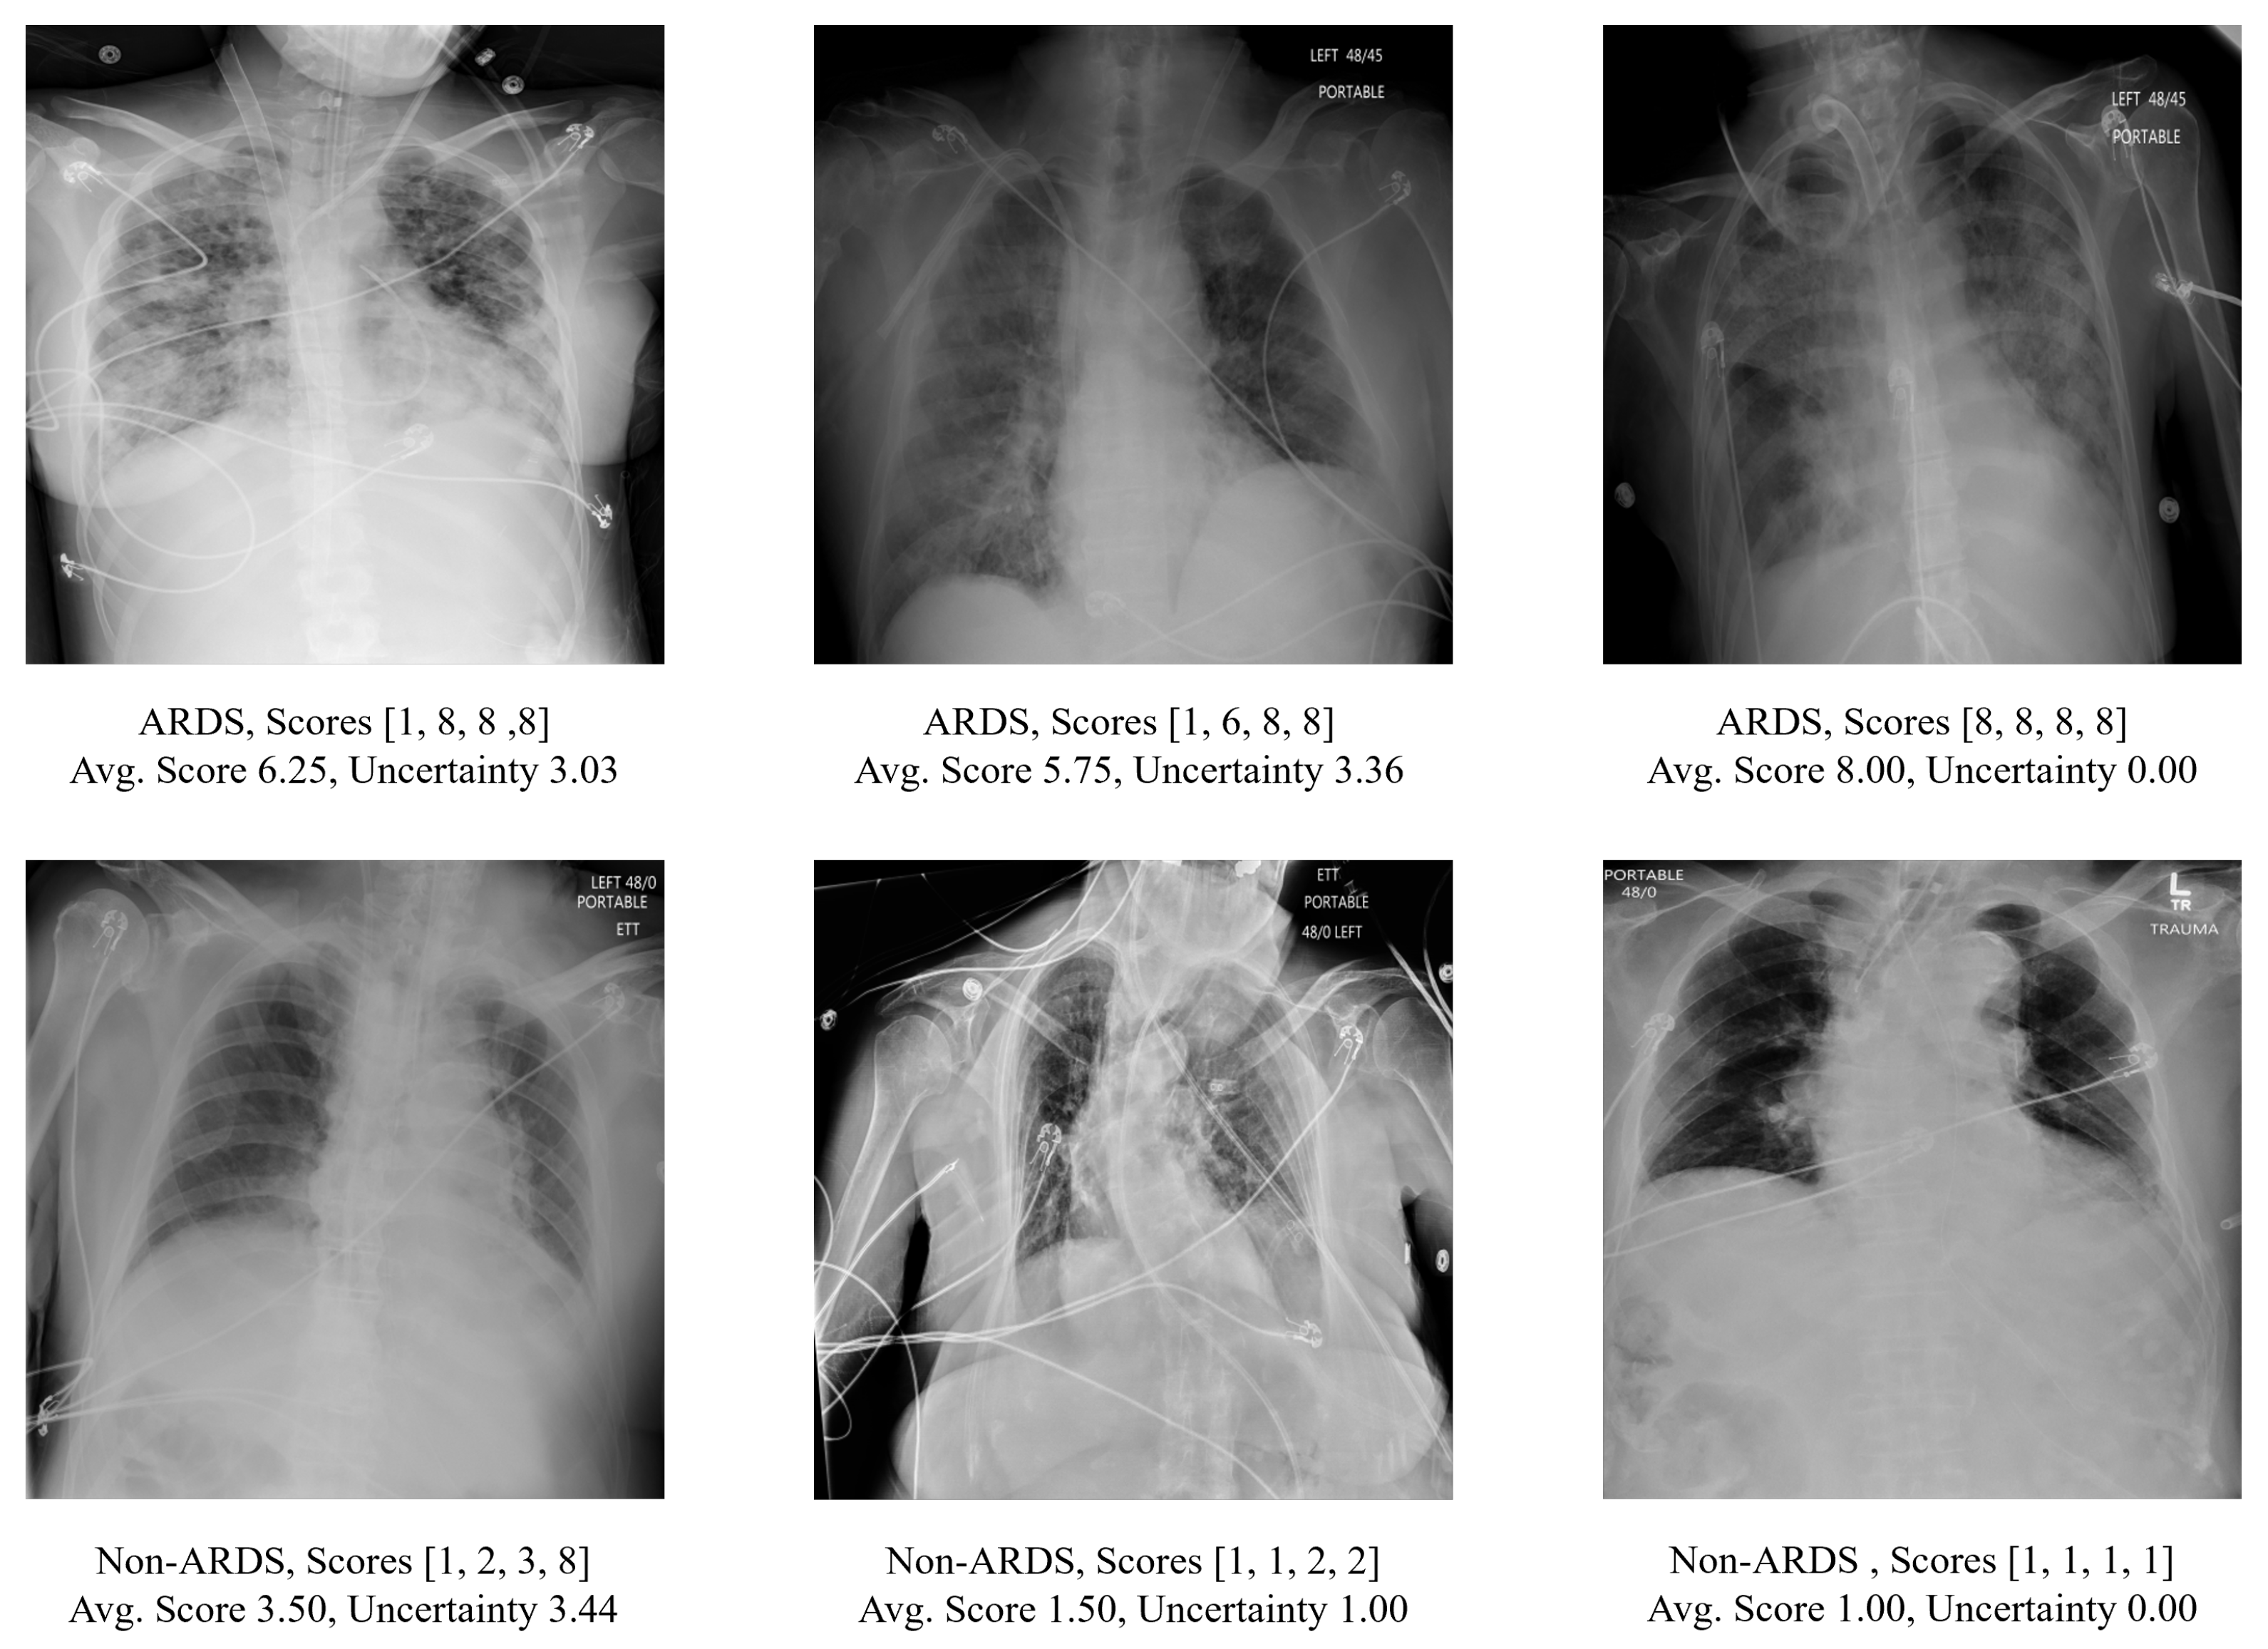

Examples of CXRs in this dataset are shown in Figure 1. Since the CXRs were obtained from hospitalized settings, they exhibited a wide range of variations and complexities. These include variations in image quality such as dynamic range and sharpness, the presence of medical devices or implants, and the manifestation of the disease itself. In total, the cohort consisted of 3055 anteroposterior (AP) CXRs from 500 patients. As depicted in Table 1, 2050 CXRs from 333 patients admitted in 2016 were used in training, while 1005 CXRs from 167 patients admitted in 2017 were designated as the hold-out test set, with no patient overlap in the data split. Among these 500 patients, 309 were male and 191 were female. The average age of the patients was 57.65 years, with a standard deviation of 16.32 years. Further information regarding patient demographics can be found in Table 2.

Figure 1.

The upper panel displays the CXR scans of patients diagnosed with ARDS, while the lower panel shows scans of patients without ARDS. The score array represents the annotation score provided by multiple reviewers together with the averaged score and the corresponding measurement of uncertainty (as defined in Section 2.3).